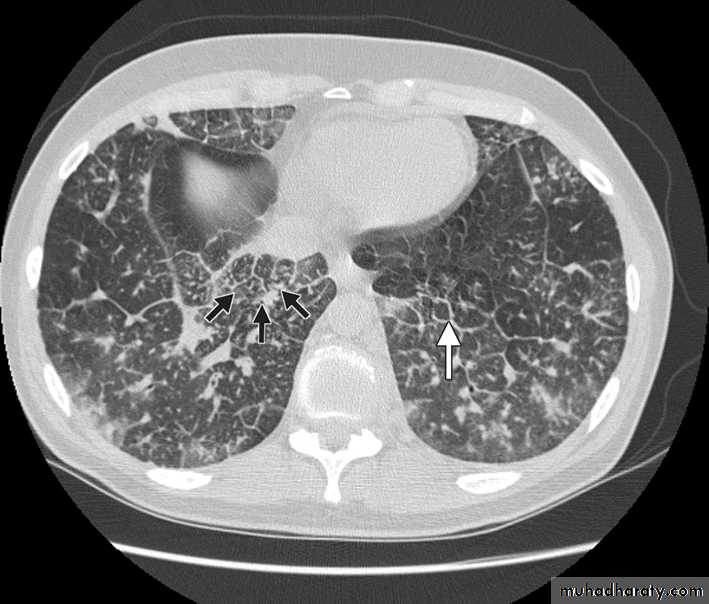

Chest CT scan shows multiple round nodules and masses of varying sizes in both lungs, consistent with metastases. There are also small bilateral pleural effusions.

Computed tomography scan showing nodular thickening of interlobular septa (white arrow), seen as polygonal arcades with thickened and nodular limbs, and ground-glass opacities (black arrows).